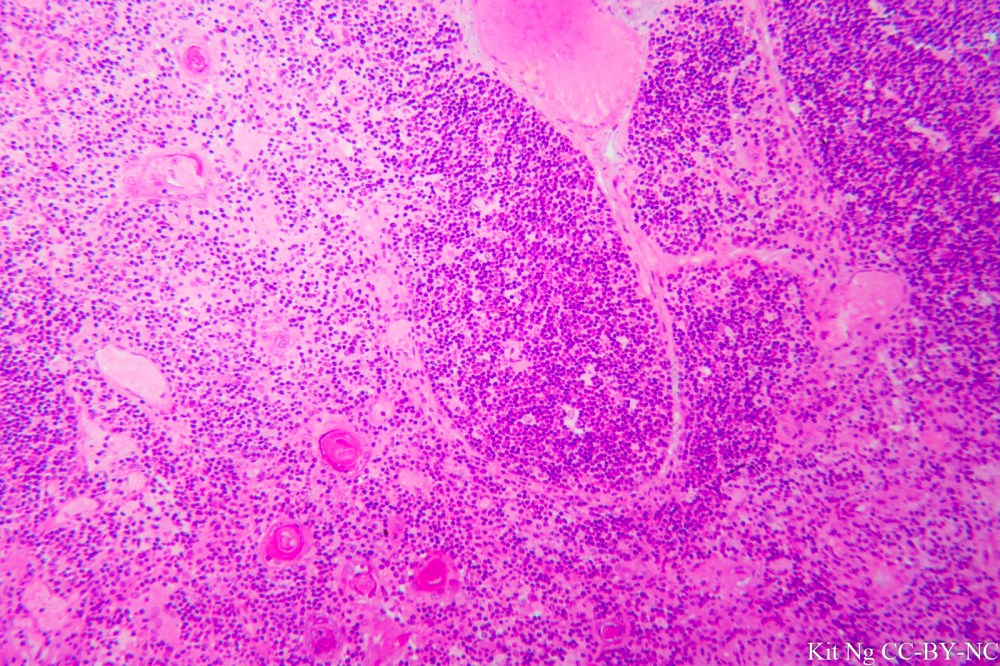

Histologically, each thymus lobule has a cortex (the outside, darker colored portion) and a medulla. In particular, the thymus is distinguished by a structure known as Hassall’s Corpuscle that has an unknown function.